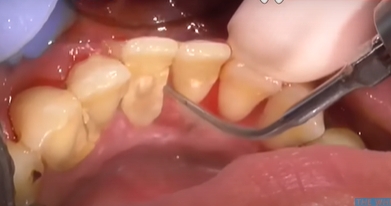

하지만 사실 구멍이 생겼다기보단 치석 아래에 있던 원래의 치아 구조가 드러난 것일 뿐이며 다만 이 공간이 음식물이나 세균에 노출되면 문제가 생기므로 그대로 방치하기보단 적절한 조치를 취하는 게 중요합니다.

치석 떨어짐 구멍 채우는 방법

첫 번째로 플러그 또는 레진으로 채우는 방법입니다. 구멍이 작지만 음식물이 자주 끼거나 시린 증상이 심한 경우에는 치아색의 레진으로 메워주는 방법을 씁니다. 심미적으로도 깔끔하고 시림 현상을 줄이는 데 도움이 됩니다.

두 번째로 잇몸이 많이 내려가서 생긴 구멍이라면 스케일링 후 치주 치료를 통해 잇몸 회복을 유도하거나 잇몸이식을 진행하기도 합니다.